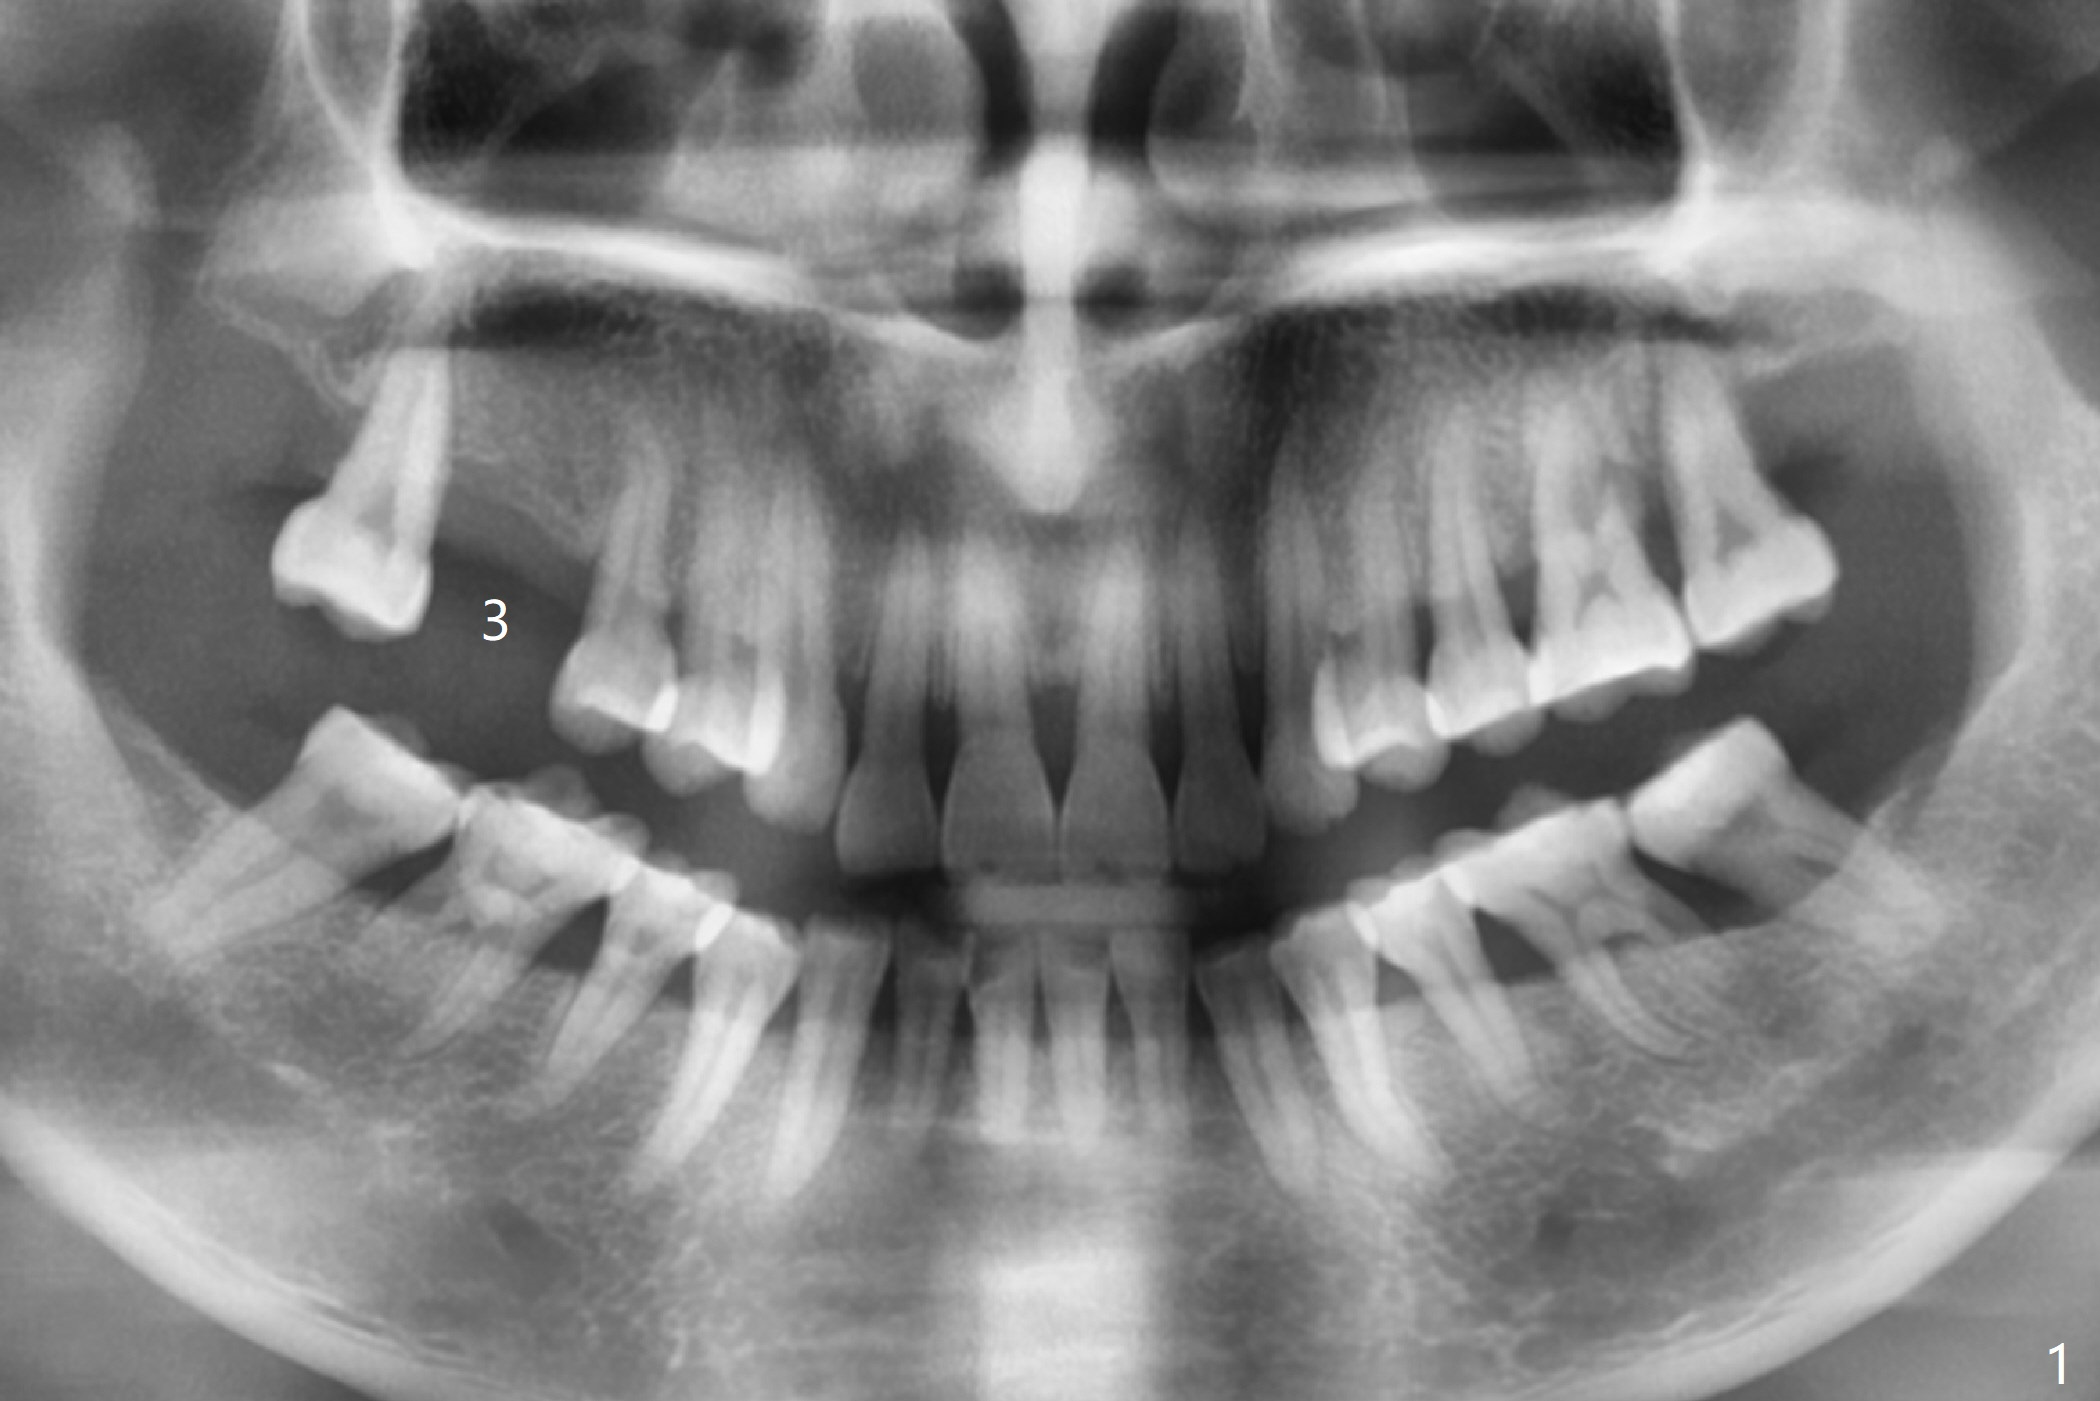

A 47-year-old woman requests implant at #3 (Fig.1). There is generalized bone loss with fair oral hygiene. It suggests bruxism. Night guard will be recommended. The patient appreciates the opportunity of having an implant with guided surgery (Fig.2). In fact the root tip of the upper right 2nd premolar curves distal. A 5x11.5 mm implant placed has limited clearance. The blood supply may be compromised.

While waiting for the surgical guide, the tooth #15 has periodontal infection (Fig.1). Immediate implant will be done first.